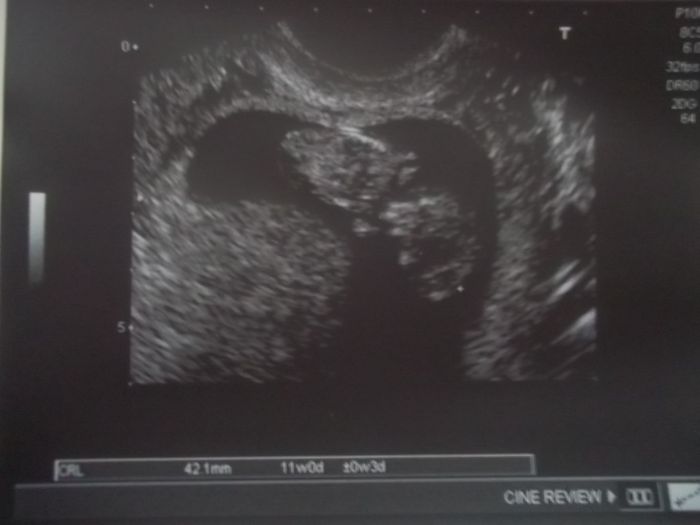

Zdravím maminky, také mám termín v červenci a to 27.7. Jsem ve 13. týdnu čekáme s manželem druhé dítko a z prvního manželství mám 18 a 15letou dceru